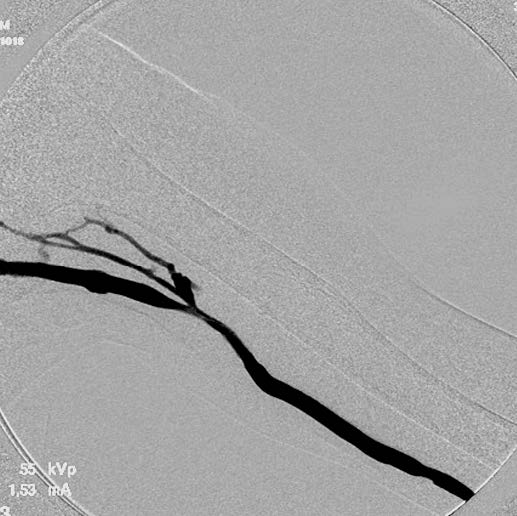

血栓除去+バルーン拡張: 人工血管を切開し、エコーガイド下にて4 Fr血栓除去カテーテルを用いて人工血管内の血栓を除去した。血流再開後のエコーで人工血管流出路静脈の高度狭窄を認めたため、人工血管に6Frシースを挿入して血管造影で確認したのち(図1)、6 mmのコンクエスト®*を用いて病変部を拡張した。最大30気圧まで加圧し、バルーンの完全拡張を得たが、PTA 後の血管造影でエラスティックリコイルを認めた(図2)。